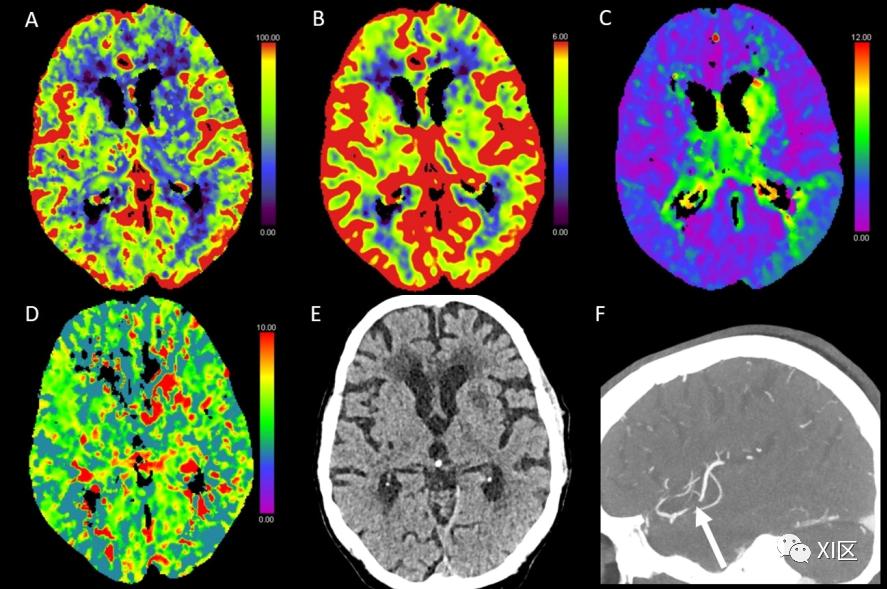

图1、图2、图3和图4给出了急性幕上卒中的例子。图5是一个恶性右侧MCA梗死的随访检查。

图4 脑部CTP产生的彩色编码图:(A)脑血流量(CBF)[mL/100 g/min],(B)脑血容量(CBV)[mL/100 g],(C)Tmax [s],以及(D)平均通过时间(MTT)[s]。(E)NECT和(F)动脉CT血管成像(CTA)。该患者表现为左侧面瘫、失语和右臂瘫痪。NECT显示左侧基底神经节区域开始出现低密度分界,并有轻微肿胀。CBF减少,CBV仅部分减少,Tmax和MTT部分延长,表明是急性梗塞。在CTA检查中,大脑中动脉(MCA)的下动脉主干出现闭塞,这解释了左侧颞叶的Tmax轻微延长。